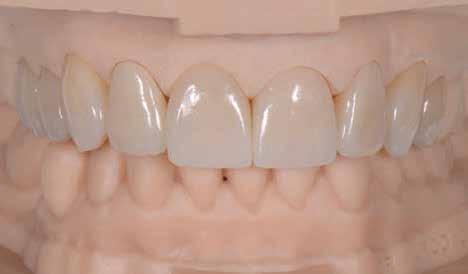

A szakirodalomban fellelhető eredmények alapján kerámia héjak ragasztására a kontaminációtól mentes, frissen vágott zománc felszín a legalkalmasabb. A hosszú távú sikeresség elérésének további feltétele a fogak konzervatív módon történő preparálása, továbbá a ragasztás kofferdám felhelyezésével biztosított, abszolút izolálásban történő kivitelezése. Úgy véljük, hogy a fenti faktorok biztosították a cikkben bemutatásra kerülő esetek – 5 évvel az átadás után megfigyelhető – sikerességét. A kofferdám izolálás alkalmazása számos előnyt biztosít a gyakorló fogorvos számára. Megakadályozza a munkaterület nyállal, vérrel, vagy szulkusz-váladékkal történő kontaminációját, és javítja a kezelendő területre való rálátásunkat. A fogak kerámia héjak ragasztása előtt történő izolálása azonban gyakran kihívást jelenthet a kevesebb klinikai tapasztalattal rendelkező fogorvosok számára. Jelen esetbemutatásban ismertetjük a kofferdám felhelyezésének lépéseit és néhány olyan gyakorlati tanácsot, amelyek jelentősen megkönnyíthetik a munkánkat, azokban az esetekben, amikor a második kisőrlőfogak közti területet kívánjuk kofferdám segítségével izolálni. A kofferdám kapcsok segítségével került rögzítésre, majd fogakat körülvevő széleit óvatosan az ínybarázdába forgattuk. A kerámia héjak számára előkészített fogakra ragasztás előtt egyenként kapcsokat helyeztünk annak érdekében, hogy a kerámia héjak rögzítése ideális körülmények között történhessen. A lépések részletes ismertetése segítséget jelenthet – a kevesebb klinikai tapasztalattal rendelkező fogorvosok számára – az abszolút izolálás megvalósításához szükséges lágyrészmenedzsment megértéséhez. Ezek az ismeretek rendkívül hasznosak lehetnek, ha a jövőben a kerámia héjak ragasztását megfelelő módon megvalósított kofferdám izolálás mellett kívánják kivitelezni. A cikkben ismertetett módszerek alkalmazásával az abszolút izolálás megvalósítható, a gumilepedő – vérzés nélkül – ínybarázdába történő beforgatására, és a ragasztáshoz szükséges idő csökkentésére.

Az oxigén inhibíciós réteg kialakulásának elkerülése érdekében a kerámiafelszíneket glicerin géllel (Liquid Strip, Ivoclar Vivadent, Schaan, Liechtenstein) borítottuk, majd ezeket a felszíneket ismét 20-20 másodpercen keresztül világítottuk. A végeredmény megfelelt a páciens esztétikai igényeinek (6. a. ábra). Az átadott restaurátumok épségének megőrzése érdekében, a páciens számára éjszakai fogvédő sín készült. Az ötéves kontroll alkalmával megállapítottuk, hogy az elvégzett kezelésünk továbbra is sikeresnek tekinthető (6. b. ábra)

Az általunk alkalmazott adhezív rendszerek hatékonyságát nagymértékben növelhetjük azáltal, hogy a fogakat minimál invazív módon, azaz csak zománcon belül preparáljuk, és a kerámia héjakat kofferdám izolálásban ragasztjuk. Jelen esetismertetésünknek az volt a célja, hogy bemutassuk, hogyan lehet az adekvát módon kivitelezett kofferdám izolálással megelőzni

a munkaterület nyállal, vérrel vagy szulkusz-váladékkal történő kontaminációját. A megfelelő méretben kialakított perforációs nyílások és köztük lévő optimális távolság elengedhetetlen ahhoz, hogy a kofferdámot ideális módon tudjuk felhelyezni. Ezzel az esettel azt is bizonyítjuk, hogy a gumilepedő levegőfújással, fogselyemmel és teflonszalagok segítségével történő beforgatásával az ínyvérzés kialakulását el lehet kerülni. Ismételten szeretnénk hangsúlyozni, hogy a megfelelő kofferdám kapcsok használata nélkül nem tudtuk volna a preparált csonkszélt a gumilepedő szélétől eltartani. A kezelés során elért eredményeket jól alátámasztotta, hogy a páciens az ötéves kontroll vizsgálat során teljesen elégedett volt.